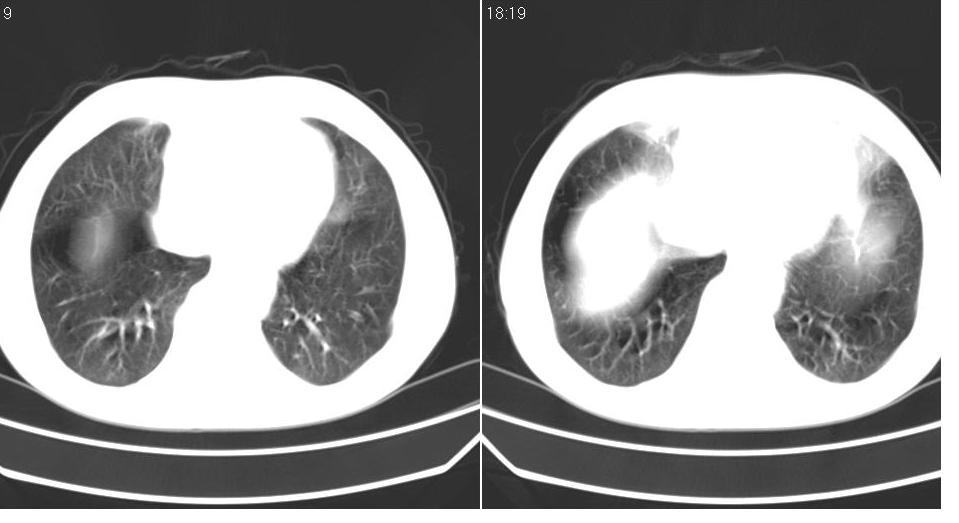

男 60岁,咳嗽,喀痰,胸闷,有吸烟史,正常图片未上传,请谅解。

左肺肿块有分叶、有毛刺,符合周围型肺癌。

分叶状肿块,有毛刺,有晕,有粗纹理直通肺门,支持考虑周围型肺癌